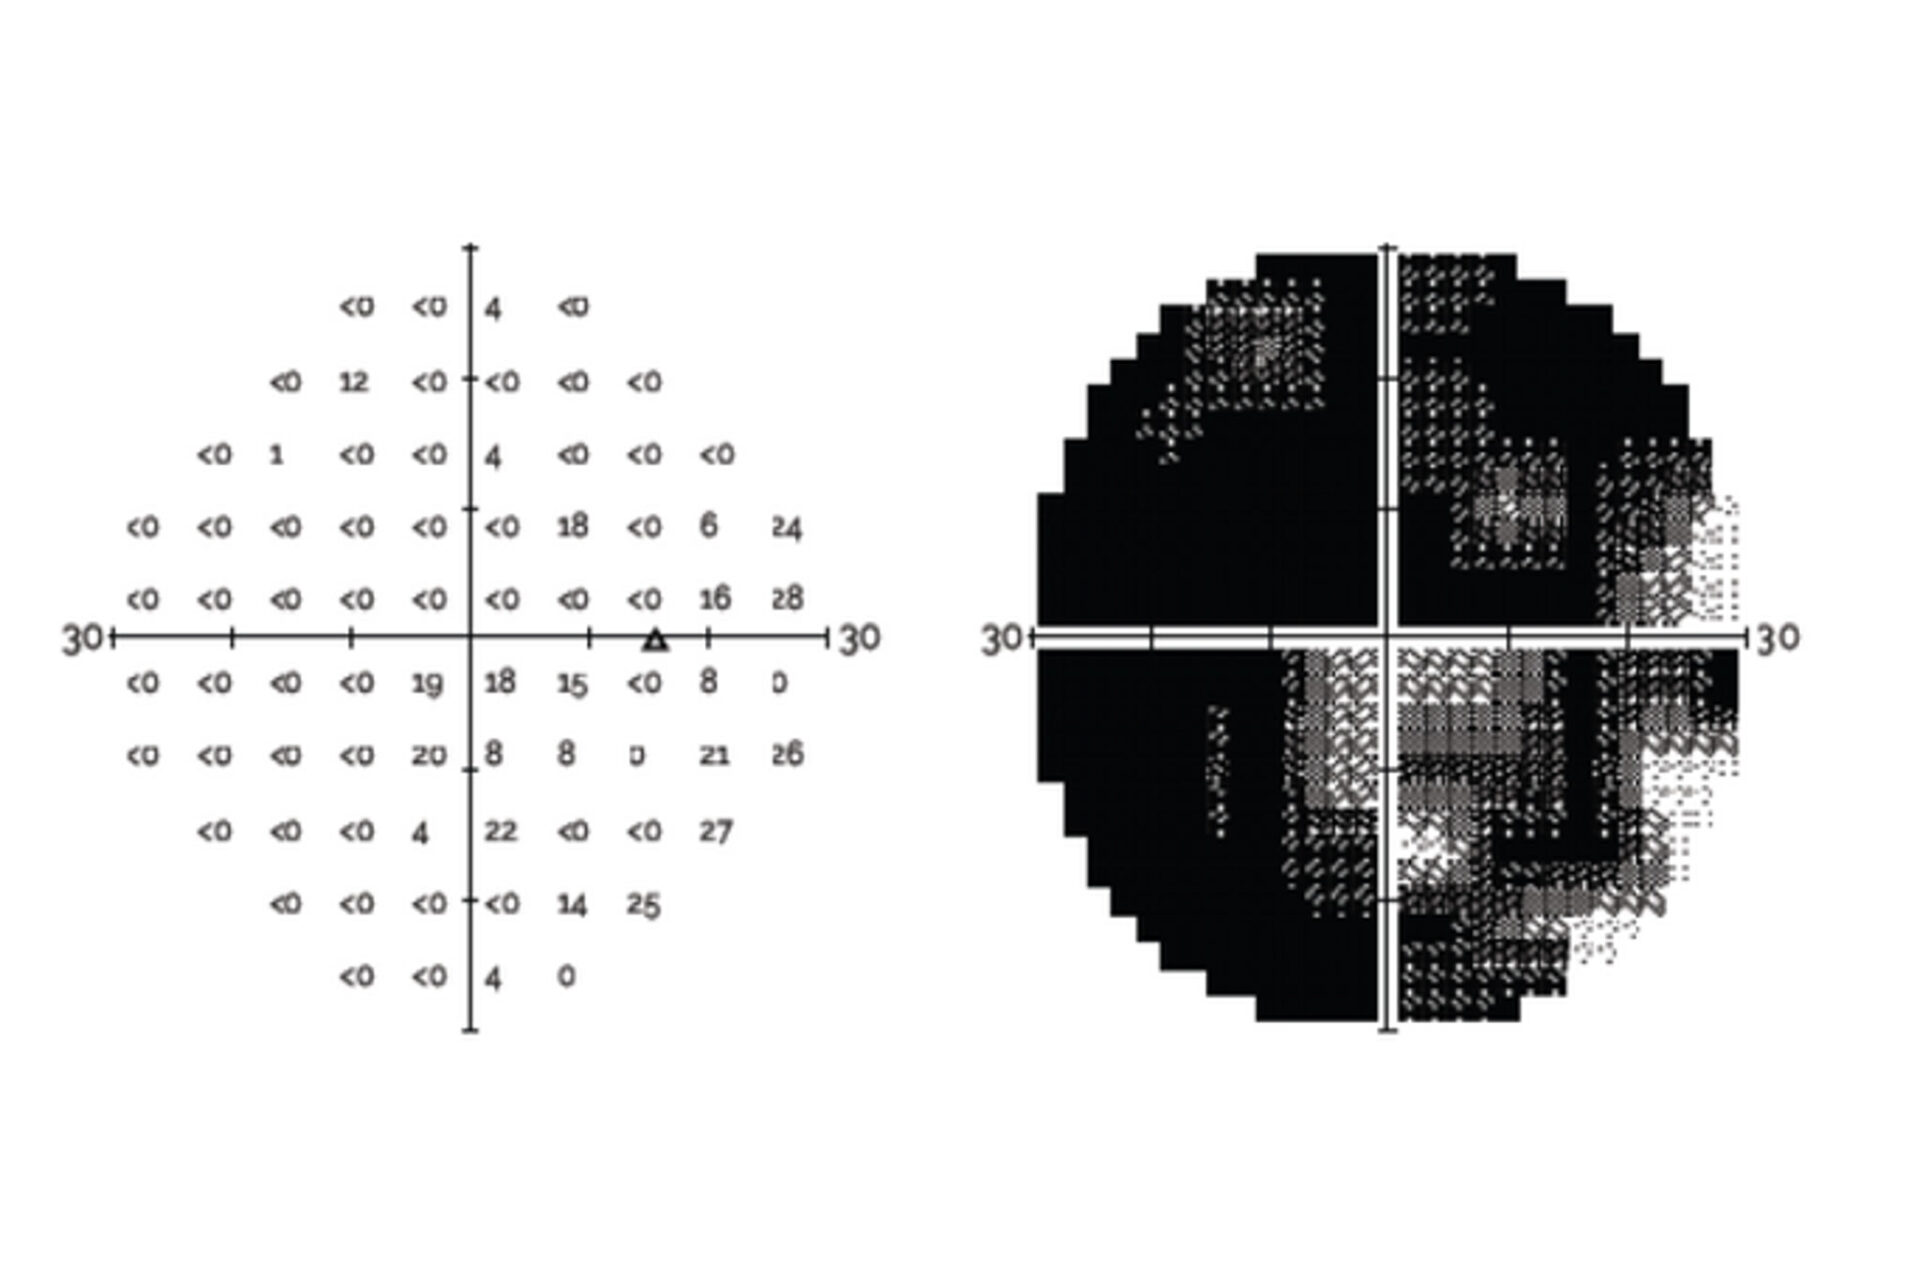

Evaluation of a Virtual Reality-Based Device (RVF100) for Visual Field Testing: A Comparison with the Humphrey Visual Field Analyzer

Compares VR perimetry results from the RetinaLogik RVF100 with the gold-standard Humphrey Visual Field Analyzer, showing strong alignment across key visual field metrics and supporting its use as a reliable alternative in clinical practice. (Under Review)

Inter-test Comparability of a Novel VR Perimetry Device with the Humphrey Visual Field Analyzer

Evaluates the alignment between VR perimetry results and the gold-standard HFA, analyzing multiple visual field metrics to determine clinical equivalence. (COS 2024)

Advancing Ocular Diagnostics: A Comparative Study Between the RVF100 Portable Virtual Reality Device and the Humphrey Visual Field Analyzer for Glaucoma Suspect Assessment

An ARVO 2024 study comparing the RetinaLogik RVF100 to the Humphrey Visual Field Analyzer in glaucoma suspect evaluations found strong correlation across all key metrics (MD, PSD, MS), with performance comparable to gold-standard testing—supporting VR perimetry as a validated, portable, and cost-effective alternative. (ARVO 2024)